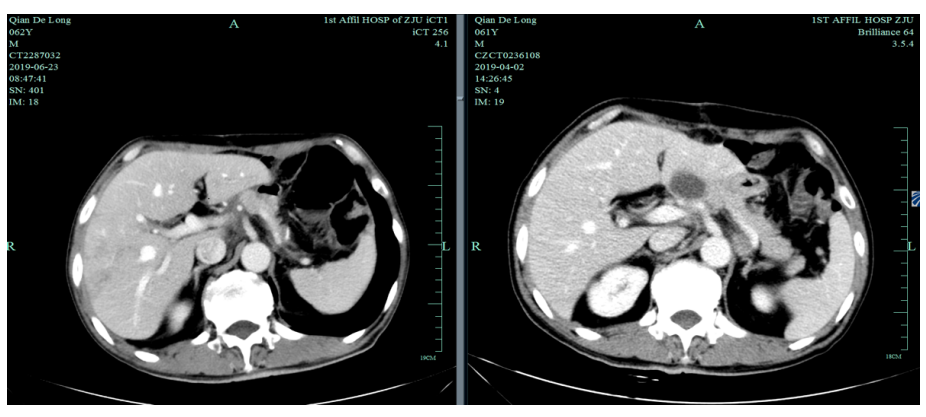

2019-4-2至2019-6-5行SOX+赫赛汀 q3w 4周期联合化疗:具体为奥沙利铂220mgD1、替吉奥3# BID D1-14、赫赛汀400mg(首次)+300mg。

一线化疗疗效评估(2019.6 vs 2019.4):胃癌术后改变。影像评估CR。

2019-12-20至2020-7-6行SPA+赫赛汀 q3w  8周期联合化疗:白蛋白紫杉醇250mg、替吉奥3# BID D1-14、赫赛汀 300mg D1 。

影像学评估:胃癌术后改变。持续CR。

2020-11-3全腹部CT平扫+增强提示胃癌术后改变,术周及腹膜后多发肿大淋巴结显示,对照2020-7-7CT淋巴结肿大进展,结合临床疗效评估PD。